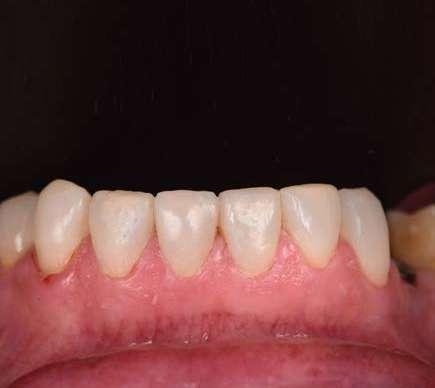

Para la arcada inferior se optó por unas carillas inyectadas, completamente respetuosas con los tejidos, que nos permiten mejorar la apariencia de los dientes y dar así una mayor armonía con la parte superior. Al ser también planificadas digitalmente aseguramos que lo que colocamos en boca sea una fiel reproducción del diseño previamente aceptado por el paciente y el profesional.

La preparación previa junto a la preparación guiada, resultaron en un equilibrio ideal para los espesores mínimos que requería el caso. Se realizó una prueba en seco para valorar el ajuste final de las restauraciones.

Consiguiendo así una perfecta adaptación de los márgenes de las restauraciones y la sensación de naturalidad e integración que se observa en la imagen final.

Como se puede observar en la imagen comparativa, la planificación se reproduce de una forma fiel a lo que se había planificado y aceptado por la paciente. Por tanto, no es una técnica susceptible al operador, que se realiza controlando mucho mejor los tiempos y los resultados obtenidos.

¡Obteniendo un caso espectacular en apenas un par de citas!